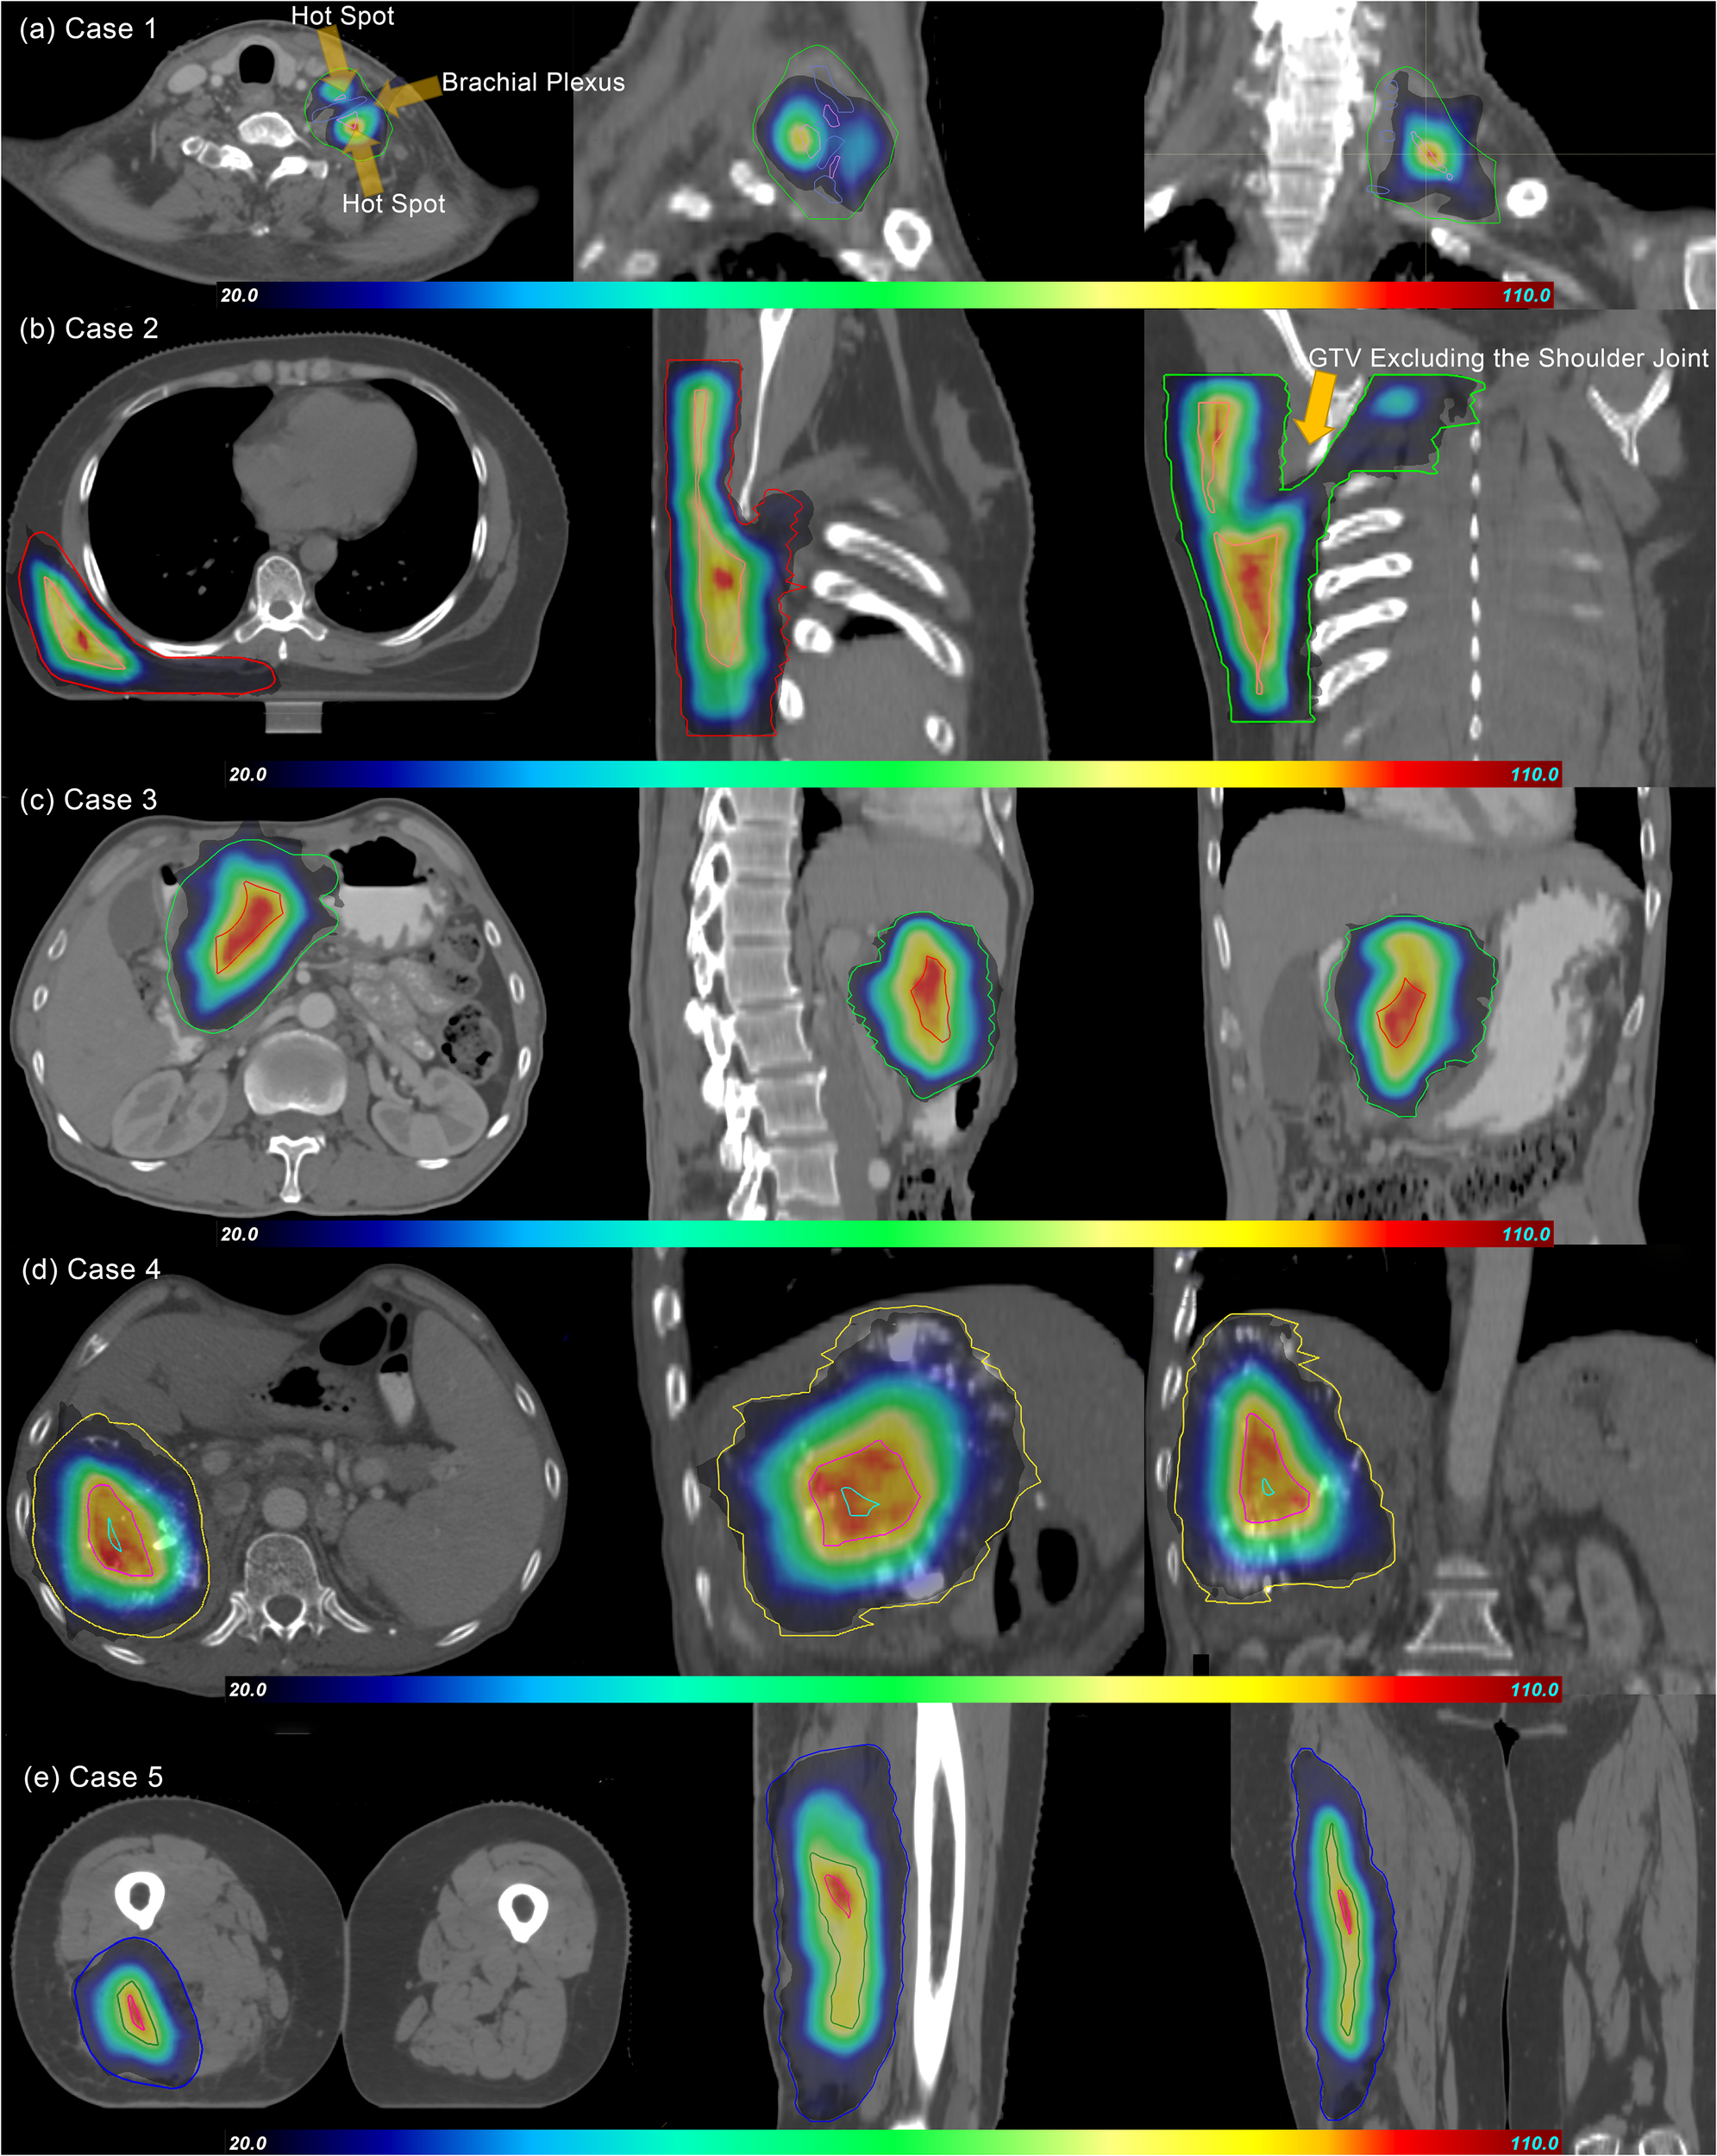

In the pSCART plans, for Cases 1 and 2, where the organs at risk were located within or near the target volume with suboptimal dose gradients, inferior conformity was observed. In contrast, superior conformity was demonstrated in the remaining cases. The dose distributions of the pSCART plans for the five evaluated cases are illustrated in Figure 1.

Figure 1

Dose distributions of pSCART treatments for the five cases. In the figure, GTV and SCTV are marked with contour lines of different colors. The dose gradient range is set from 20% to 110%, and the prescription dose is normalized with the maximum value of 100% as the benchmark. As shown in the figure, the dose volume spillage area outside GTV does not significantly exceed the 20% prescription dose threshold. Under the condition that functional imaging guidance is limited, the SCART technique theoretically should generate an SCTV with a regular geometric shape by uniformly shrinking GTV. However, in clinical practice, the areas overlapping with important serial organs like nerve plexuses (such as brachial plexus in Case 1), joint structures (such as shoulder joint in Case 2), digestive tracts, and major blood vessels, which are organs at risk (OARs), need to be excluded from SCTV to form the “SCTV-OARs” modified target area. This anatomical structure exclusion operation leads to the irregularity of SCTV in the pSCART plan. The research results show that the proton plan with active beam modulation is superior to the CyberKnife SCART plan in terms of SCTV coverage and conformity. This result is also verified by the “80% SCTV coverage” data in Table 3. SCART, stereotactic centralized/core ablative radiation therapy; pSCART, proton-based SCART; GTV, gross target volume; SCTV, stereotactic centralized/core target volumes.